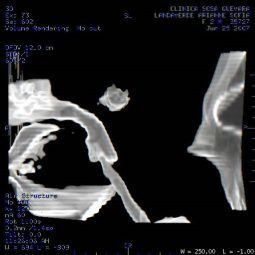

Clínica de Radiología y Ultrasonografía Sosa - Guevara

TAC de columna cervical

Clinicas > Radiologia

VER GALERÍA